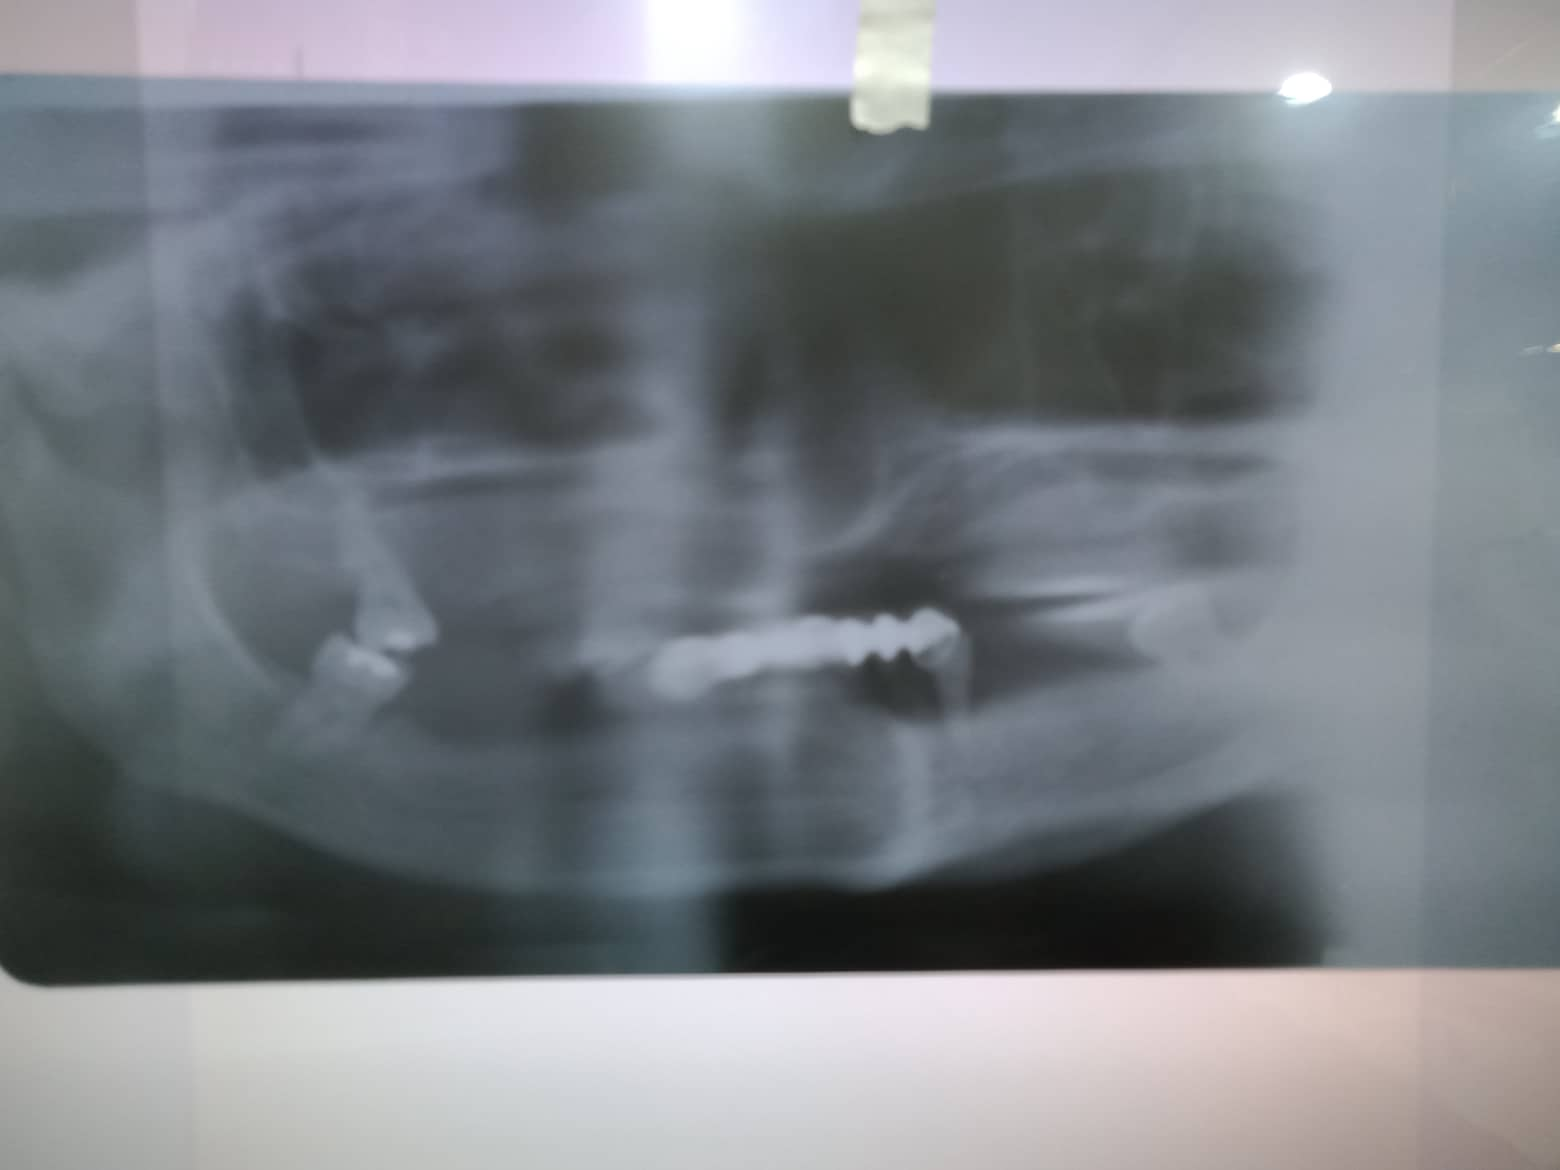

- Procedure